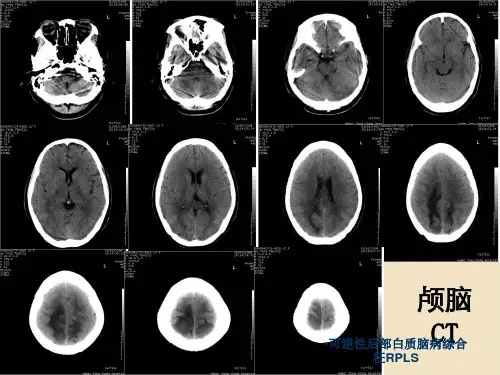

本病影像学改变的特点为皮质下白质脑水肿,以双侧 顶、枕叶最为多见,其他部位也可出现,按照出现的 频率依次为额叶、颞叶、小脑、丘脑和脑干。通常病 变白质重于灰质,后循环重于前循环。两侧基本对称, 但也可不对称,占位效应轻;

CT显示等或低密度;MRI显示T1等或低信号、T2或 FLAIR像高信号,弥散加权成像(DWI)显示等或低 信号,且T2异常信号区域主要为血管源性水肿而非细 胞毒性水肿。